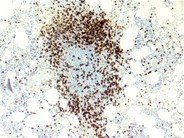

Post-polycythemic myelofibrosis, bone marrow core 1 from imagebank.hematology.org What is a bone marrow transplant? The patient is an 11 years old child with a mediastinal tumor. The marrow aspirate shows an invasion with neuroblastoma cells and characteristic images of neuropile threads. The bone marrow donor programme (bmdp) manages singapore's only register of volunteer bone marrow donors. Bone marrow edema is commonly seen with fractures and other serious bone or joint injuries, especially those involving the spine, hip, knees, or ankle. More than 35,000 people have donated bone marrow to a stranger without a single. World marrow donor association matching donors • serving patients since 1994. This image belongs to set:

Reactive bone marrow aspirate - 1. from imagebank.hematology.org If your bone marrow isn't functioning properly because of cancer or another disease, you may receive a stem cell transplant. This means they all share their registry databases and if matches between patients and donors in. The purpose of this study is to store blood, serum and bone marrow so that they can be used for laboratory studies that may contribute to finding the exact function of the cart cells and the factors that may determine disease progression and treatment response. After donation, donors may feel soreness in the lower back. Our modes of operation include conducting community drives for patients, working with other worldwide registries, ancestral genetic studies. Its job is to produce blood cells. Recently the use of bone marrow stem cells in regenerative medicine has also been tried with excellent success. Among the widely acknowledged and universally accepted stem cell treatments, since the very evolution of medicine, are bone marrow therapies for an array of hematopoietic disorders.